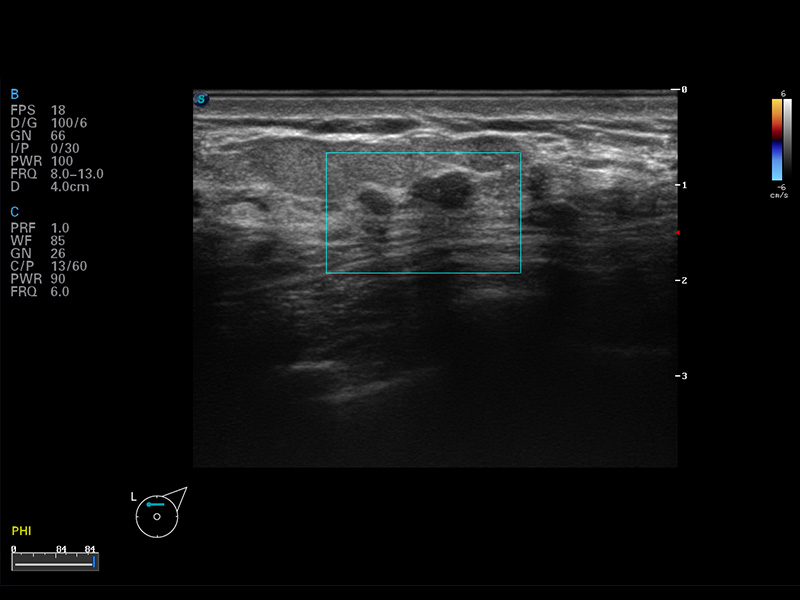

S8 EXP便携式彩色多普勒超声诊断仪是美狮贵宾会官网研发的高端全身应用型便携彩超。高通道的VIS平台融合可视化(Visual)、智能化(Intelligent)和人性化(Smart)的特点,配以美狮贵宾会官网自主研发生产的探头大家族,使您能够快速、准确的获得病人信息,提高工作效率的同时减轻疲劳。

μ-Scan微米成像